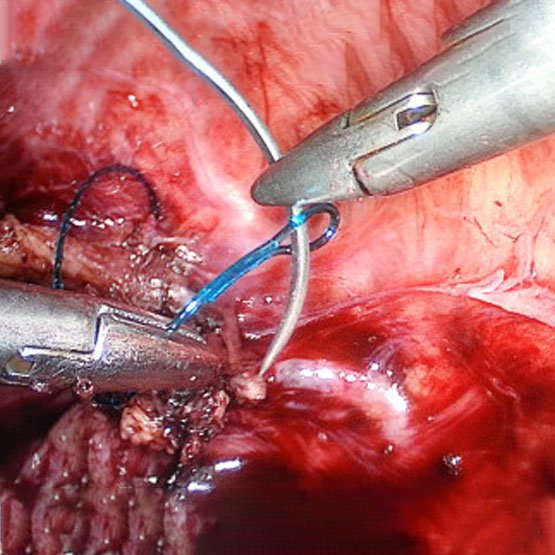

ByRL LAPAROSCOPIC NEEDLE HOLDER

Needle Holders are used to grasp and manipulate suture needles to enable free-hand Endo-suturing of wounds or surgical incisions with in the body during Laparoscopic procedures. These are used in almost all Laparoscopic Surgeries, Urology, General Surgery, Onco Surgery, Gynaecology, Gastroenterology, Bariatric / Obesity Surgery and Paediatric Surgery.

Product Features:

- The tungsten carbide jaws ensure stable, secure holding of the needle and suture material while still being highly resistant.

- The smooth-running, precisely settable ratchet facilitates secure positioning of the needle

- Antislip surface on handle provides firm and safe grip.

- Deeper slits on the jaws ensures firm and strong grip of needle and doesn’t allow slipping off the needle during endo-suturing.

- The ergonomic design of the handles allows relaxed and precise work

- A new needle holder with a needle righting function. The needle holder offers significant time and handling advantages, especially for interrupted suturing. The needle, which is clamped flat in the needle holder, can be raised at the site by means of the rotary wheel.

- Available in 4 types of Jaws:-

- Straight Jaws

- Self Righting Jaws

- Curved Jaws

- Toothed Jaw

- Available in sizes 3mm, 5mm and 10mm with length 30cm, 33cm & 43cm or any customised length